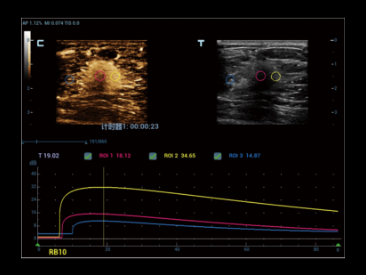

Совершенно новый способ продемонстрировать 2D цвет/мощность, инновационный доплеровский поток в 3D- визуализации.

Glazing Flow обеспечивает четкую визуализацию структуры дугообразной артерии и малой междольковой артерии с трехмерным изображением.